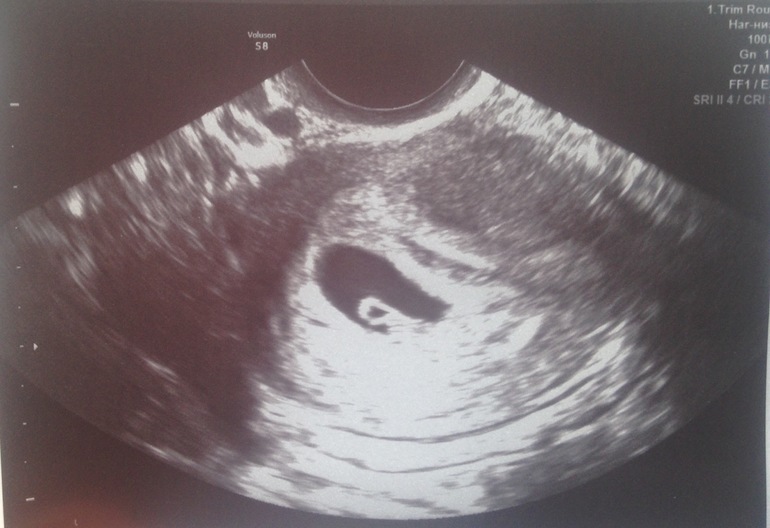

Первое узи впечатления😍

УЗИ, КТГ, доплерДень добрый)) поделюсь эмоциями, так как они у меня зашкаливают) так было волнительно перед узи) было трансвагинально, как вы и писали видео не делали, срок маленький и вообще очень быстро все посмотрели, наверно даже и 10 минут не была)) сердечко есть 138 чсс)) сказали все хорошо, единственное узистка увидела кисту небольшую, успокаивала, что рассосётся )) снимок сделали, я попросила и не отказали)) и на фото я почему-то отчётливо живо нарисованное сердце как детстве когда рисуешь сердечки 🙈❤️